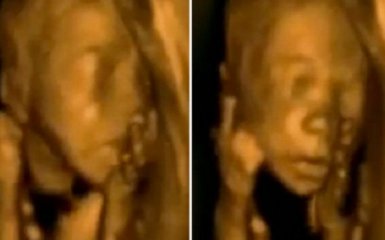

Видео четырехмерного ультразвукового исследования с танцем ребенка в утробе матери стало хитом социальной сети Facebook.

Видеоролик, опубликованный на странице украинского подразделения медицинского портала Meddy Bear в соцсети, демонстрирует движения и поведение малыша в утробе матери, пишет  Mirror.

Ролик, появившийся в сети 19 декабря, набрал свыше 8 миллионов просмотров и более 45 тысяч лайков на Facebook.